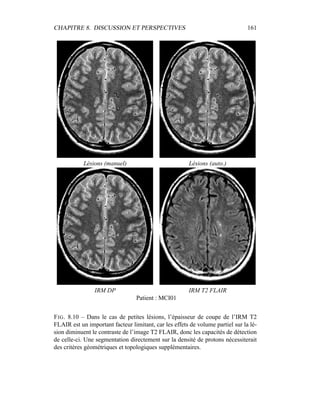

V. Dousset, M. Savoiardo, and J. S. Wolinsky. Magnetic resonance tech-

niques for the in vivo assessment of multiple sclerosis pathology: con-

sensus report of the white matter study group. J Magn Reson Imaging,

21(6) :669–675, 2005.